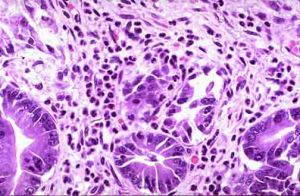

急性胃炎的病理表現(三)小腸疾病:主要表現有臍周腹痛、腹脹和腹瀉,糞便呈糊狀或水樣,當發生消化或吸收障礙時,則含消化不完全的食物成分,可伴有全身性營養缺乏的表現。常見病種有急性腸炎、腸結核、急性出血性壞死性腸炎、克羅恩病、吸收不良綜合徵、腸梗阻等。